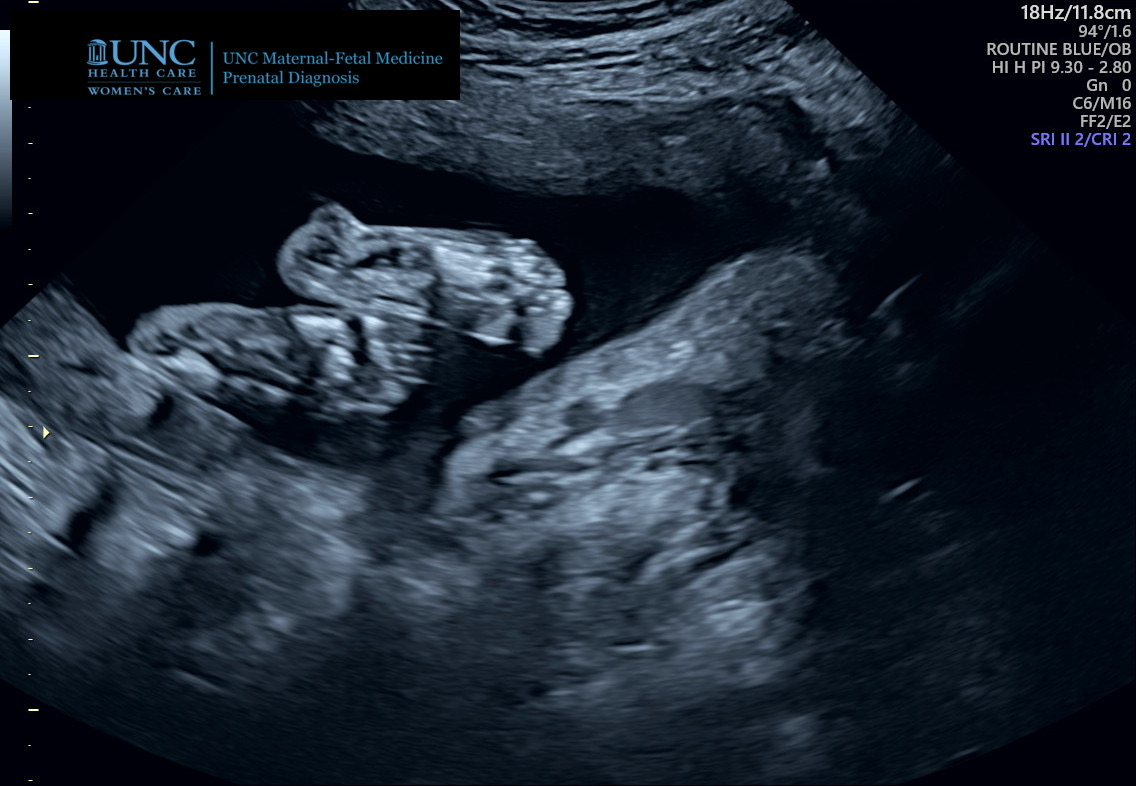

On January 23, 2021, I had my one and only ultrasound. It was quite surreal to see my baby with it’s body parts inside of my body, kicking and moving around with all it’s energy.